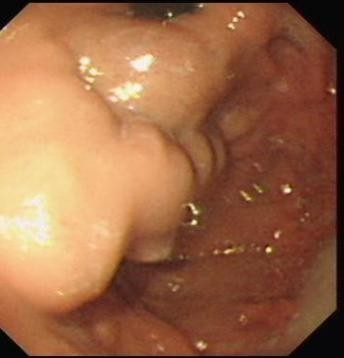

⑤ESD

随着内镜微创技术的发展,越来越多的早期消化道癌、癌前病变及胃肠黏膜下疾病可完全在内镜下予以切除,免除了更大的手术创伤,这就是内镜黏膜下剥离术ESD(endoscopic submucosal dissecfion)

该治疗具有不改变消化道解剖结构、不开刀、体表无创口、创伤、出血少、恢复快等优势,是近年来国际、国内最新兴起的内窥镜下微创治疗手段之一,适用于食管、胃、十二指肠等上消化道及结、直肠的黏膜下良性肿瘤、黏膜的早期癌变以及具有癌变倾向病变的切除治疗。因其特殊的微创优势,得到广大医生及患者的推崇,是消化道黏膜及黏膜下病变治疗的新兴发展趋势。我中心已经开展该项技术,技术成熟,并还开展了经口内镜下肌切开术POEM、内镜经粘膜下隧道肿瘤切除术STER、粘膜下隧道内镜剥离术ESTD,术后病人随访,恢复良好。

Ⅰ、ESD的治疗效果如何?

ESD治疗胃早癌可实现较高的整块切除率(92%~97%)和完整切除率(73.6%~94.7%),5年总生存率和5年疾病生存率分别为96.2%~97.1%和100%。